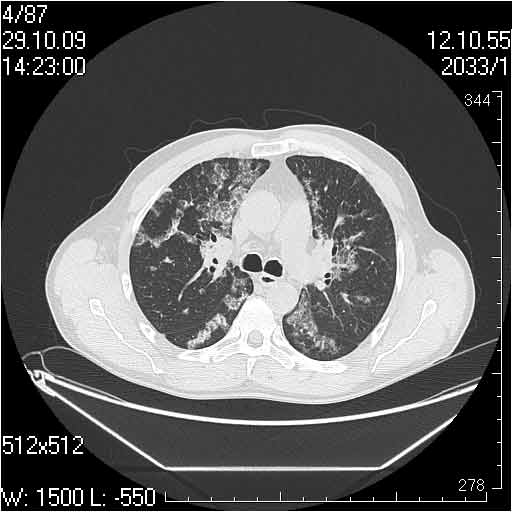

Случай №2

Мужчина 54 лет

Случай 2: картина патологических изменения довольно типична: GGOs & thickened interlobular septas = "crazy paving" sign. Наличие плотностей по типу матового стекла в сочетании с утолщением междолевых перегородок, даёт признак булыжной мостовой; на первом месте будет стоят диагноз альвеолярных протеиноз.